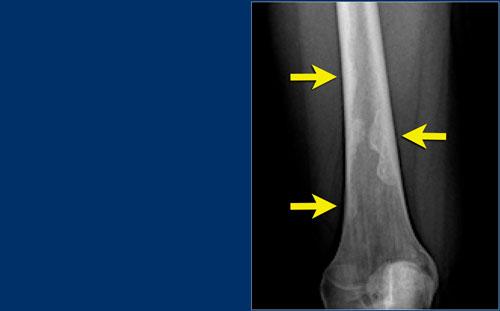

Ở đây, xơ cứng phản ứng là dấu hiệu rõ ràng nhất trên X-quang.

Có xơ cứng phản ứng với ổ tổn thương hầu như không nhìn thấy trên phim X-quang (mũi tên xanh), nhưng thấy rõ ràng trên CT (mũi tên đỏ).

Chụp CT thường rất hữu ích trong việc phát hiện ổ tổn thương trung tâm (nidus) và phân biệt u xương dạng xương (osteoid osteoma) với các tổn thương xơ cứng khác như u nguyên bào xương (osteoblastoma), viêm tủy xương (osteomyelitis), viêm khớp (arthritis), gãy xương do stress (stress fracture) và nội cốt (enostosis).

Trong hầu hết các trường hợp u xương dạng xương, hình ảnh X-quang được xác định bởi tình trạng xơ cứng phản ứng.

Tuy nhiên, trong một số trường hợp, ổ tiêu xương có thể nhìn thấy được trên phim X-quang (hình).